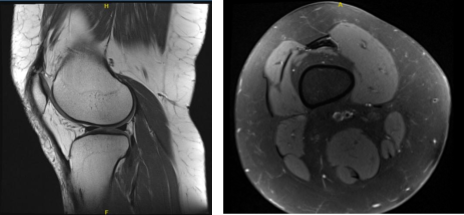

X-ray results showed that there are no significant degenerative changes and there are no fractures. The patient was advised to take an MRI in order to show the reason which caused pain in her knee.

The patient’s MRI results showed minimal chondral wear over the patella and lateral tibial plateau. No evidence of meniscal tears. Mild patellar tendinosis.

MRI Right Knee Non-contrast